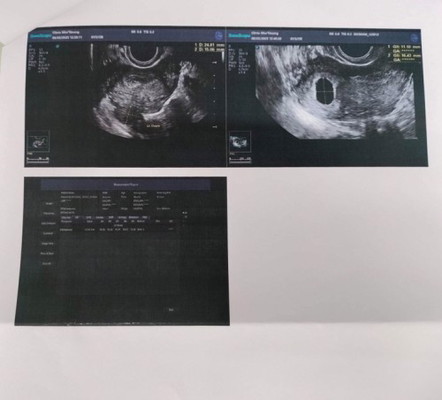

เป็นคนประจำเดือนมาไม่ตรงกันนะคะ ประจำเดือนเรามาวันที่ 12 ธ.ค หายเป็นวันที่ 16 ธ.ค มีอะไรกับแฟน 18 ธ.ค แล้วก็วันที่ 22 ธ.ค หยุดทำการบ้านไปพักหนึ่งเพราะไอมาก ต้องกินยาพวกฆ่าเชื้อแกไอก่อน แล้วก็มามีอะไรกันอีกทีวันที่ 22 ม.ค กับวันที่ 29 ม.ค หลังจากนั้นรู้สึกเวียนหัวมาก เลยซื้อที่ตรวจมาตรวจวันที่1ก.พ ขึ้นสองขีดค่ะ วันที่8ก.พ.เลยไปฝากครรภ์ที่คลินิก คุณหมอลองคร่าวๆถ้านับจากวันที่หมดประจำเดือน น่าจะเกือบ2เดือนแล้ว คุณหมอเลยซาวด์ผ่านช่องคลอดเจอถุงการตั้งครรภ์ในมดลูกแล้วค่ะ แต่ว่ายังไม่เจอตัวเด็ก หมอเลยนัดรอีก3อาทิตย์ค่อยไปตรวจใหม่เพื่อดูตัวน้องค่ะ แม่ๆท่านอื่นเคยเป็นแบบนี้ไหมคะ